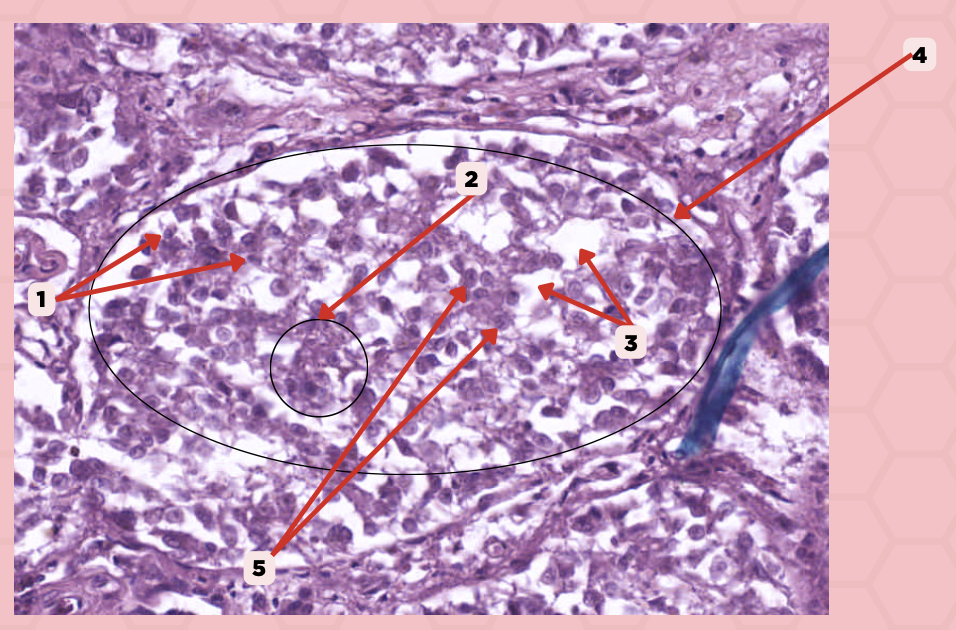

Pancreas

Identify the specimen.

Islets of Langerhans

Identify the structure labeled as 1.

Pancreatic Acini

Identify the structure labeled as 2.

Reticular Tissue

Identify the structure labeled as 3.

Pancreatic Duct

Identify the structure labeled as 1.

Reticular Tissue

Identify the structure labeled as 2.